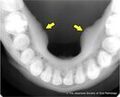

顎に発生する骨隆起は特に注目されます。顎骨隆起は、下顎(下あご)の外側や上顎の内側に現れることが多く、無症状であることがほとんどです。これらの骨隆起は、一般的に触れることができ、診断は触診やレントゲンで行われます。

レントゲンやCTスキャンでの骨隆起診断

骨隆起の診断は、通常、レントゲンやCTスキャンを使用して行われます。これらの検査は、骨の異常な成長を可視化するため、非常に有効です。また、他の疾患との鑑別診断にも重要な役割を果たします。